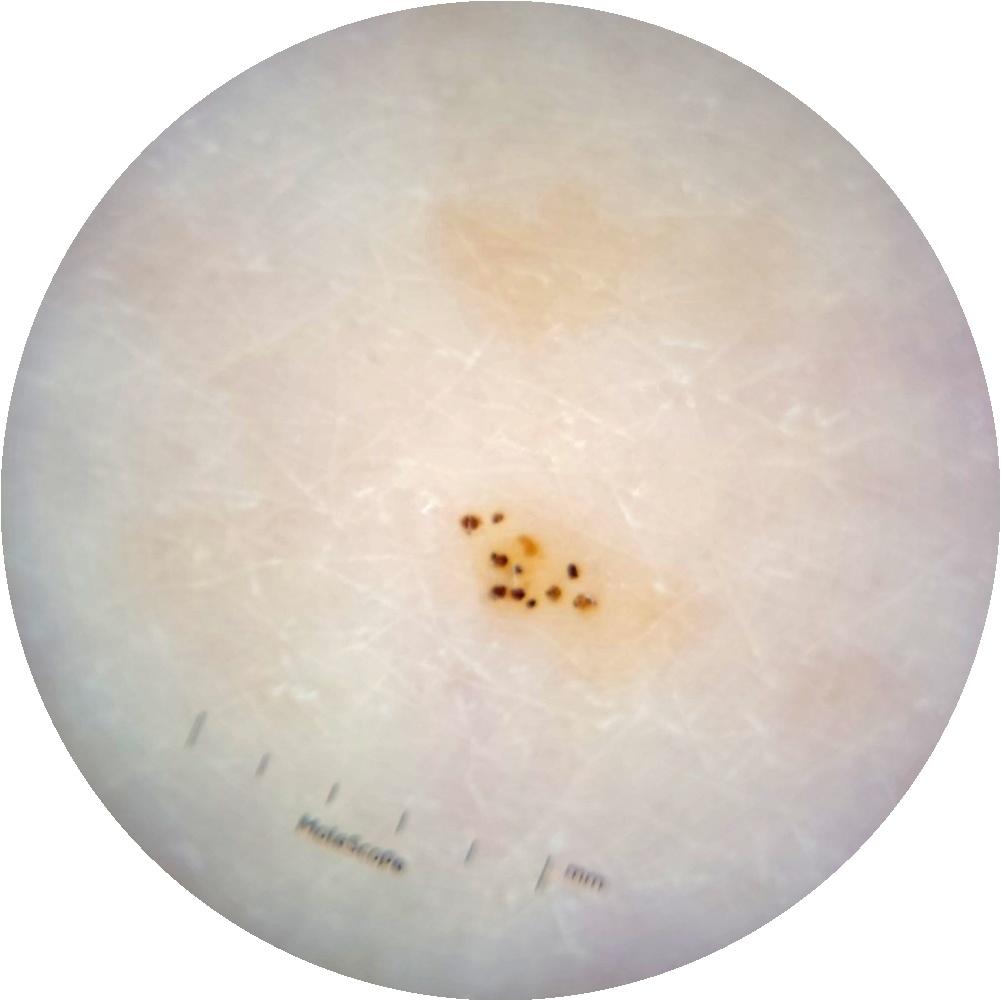

ISIC_6363669

IP_1322385

IL_2591344

anatom_site_1 Trunk

anatom_site_2 Anterior trunk

anatom_site_general anterior torso

diagnosis_1 Benign

diagnosis_confirm_type single image expert consensus

image_type dermoscopic